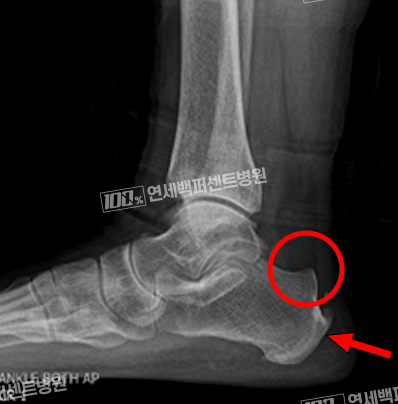

최소침습 해글런드 변형 절제술

긴 절개 없이 최소침습으로 치료!

돌출된 뒤꿈치 뼈와 아킬레스건 염증 동시 치료!

수 차례의 충격파 치료, 주사치료에 반응 없는 난치성 아킬레스건염 해결!

손OO (23.01.09)

손OO (23.03.09)